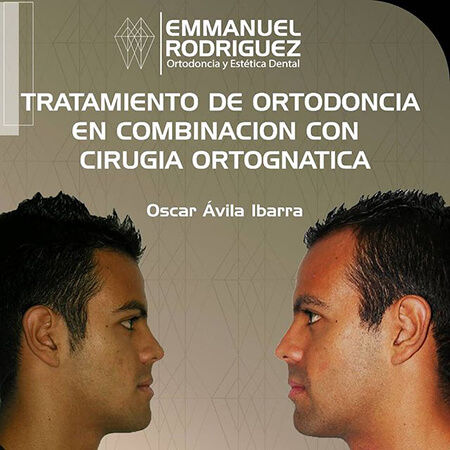

Didenti offers a wide range of services, including orthodontics, cosmetic dentistry, maxillofacial surgery, dental implants, oral rehabilitation, periodontics and endodontics. Doctors Fragozo and Rodríguez offer personalized care backed by the most advanced technology.

Before and After Gallery